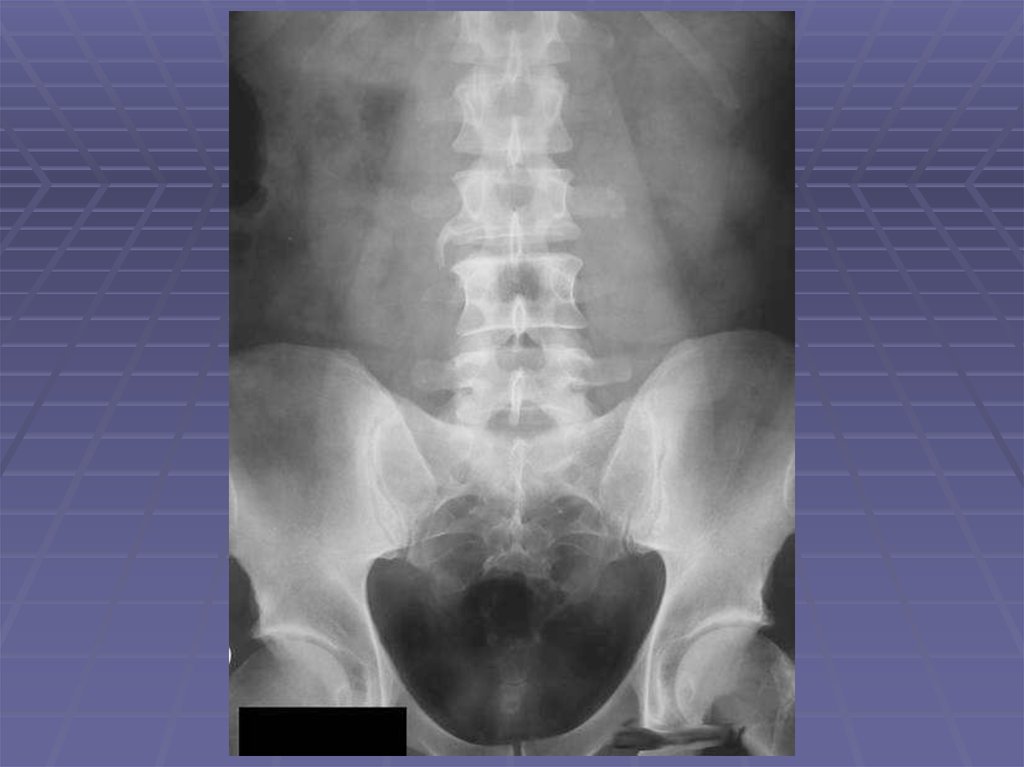

Инструментальные методы диагностики в нефрологии Читайте также: Натуралка для котов с хпн — абсцессов; — травм; — поликистоза; — гидронефроза. Опухоль почки Читайте также: Как научить ребенка читать по слогам в домашних условиях. Советы учителя начальных классов